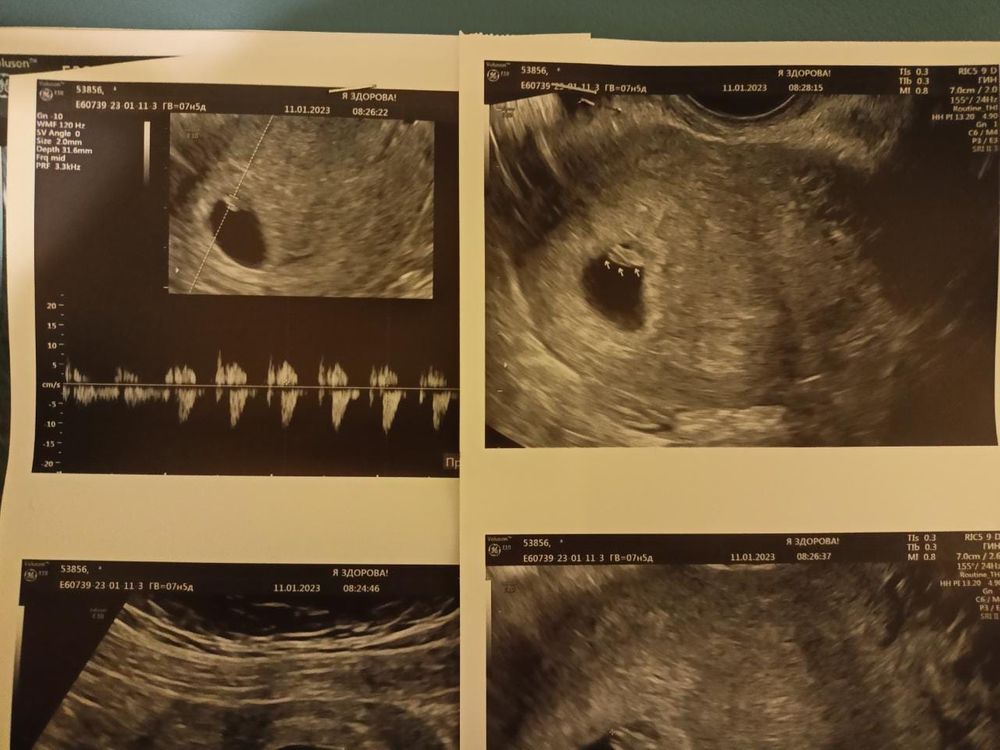

УЗИ 7 недель

Девочки, я счастлива! Растет моя фасолинка, сердечко бьется. Прошу девочек, у которых не увидели эмбрион не расстраиваться заранее. Была на УЗИ 29.12 - ПЯ было 8 мм и ЖМ - 2,8 мм, пошла 5.01, думала увижу эмбриончик, но его не увидели: ПЯ - 13,8мм, ЖМ - 5 мм намерили. С 5 января до сегодняшнего дня уже все передумала, сходила иииии Выкладываю для истории и чтобы другие девочки могли найти и увидеть информацию со схожими сроками. Я перед УЗИ много искала, смотрела Узишки и записи. Спасибо тем кто выкладывает и делится. Надеюсь, мое тоже кому то поможет и моя история кого то успокоит!

11.01.2023